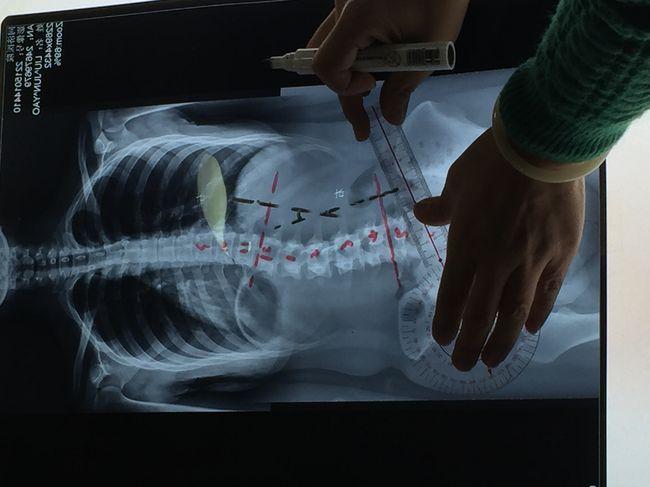

脊柱侧弯180度图片,脊柱侧弯1到10度图片

x光片上的弯曲角度大于10°时,即可以诊断为脊柱侧弯.